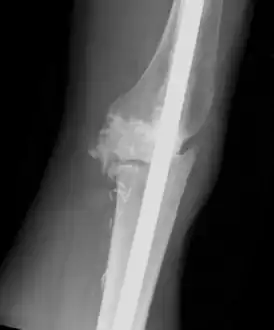

Individual with tumoral calcinosis- Lateral radiograph of the left knee demonstrating an intramedullary rod